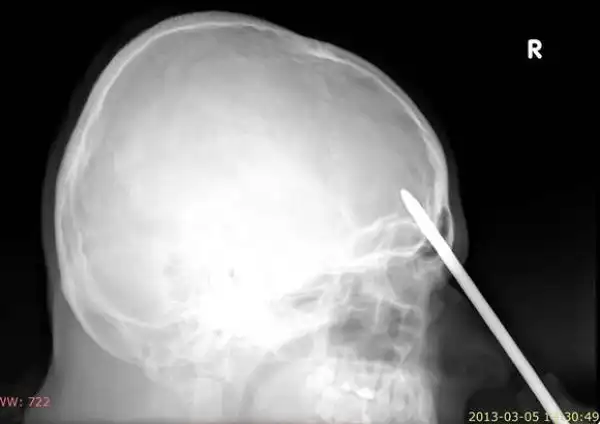

25-летний поляк трудился у себя в саду, когда потерял равновесие и упал на инструменты. Поднявшись и придя в себя он посмотрел в зеркало и обнаружил, что у него из головы торчит отвертка. Мужик не стал суетиться, а просто достал сигарету, закурил и отправился к соседу, чтобы тот помог ему добраться до больницы. Как оказалось, отвертка вошла в мозг на пять сантиметров, но очень удачно, поэтому инструмент без труда извлекли, а дырку залатали.